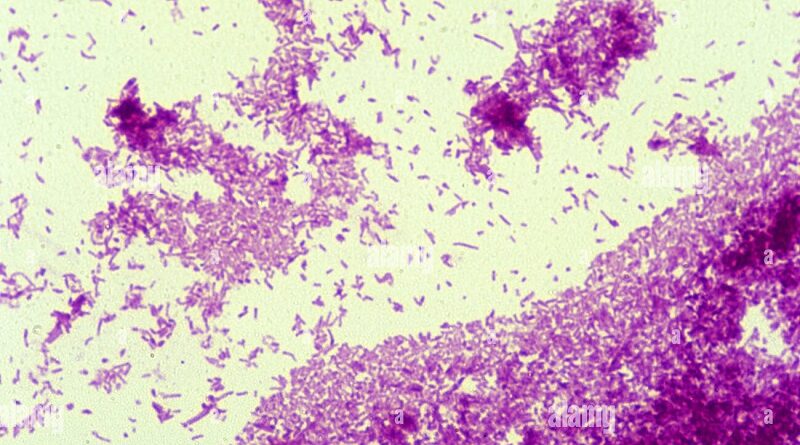

Shape of Mycobacterium tuberculosis under the microscope.

- It is a tiny, rod-shaped bacterium (Bacilli). It appears as a bright red rod (pink) when stained using the Ziehl-Neelsen stain.

- Under the microscope, it is straight or slightly curved.

- The bacterium has the following dimensions:

- Length: Approximately 2–4 µm (micrometers).

- Width: Approximately 0.2–0.5 µm.

- Its cell wall is unusually thick and waxy, which makes it challenging to penetrate with drugs.